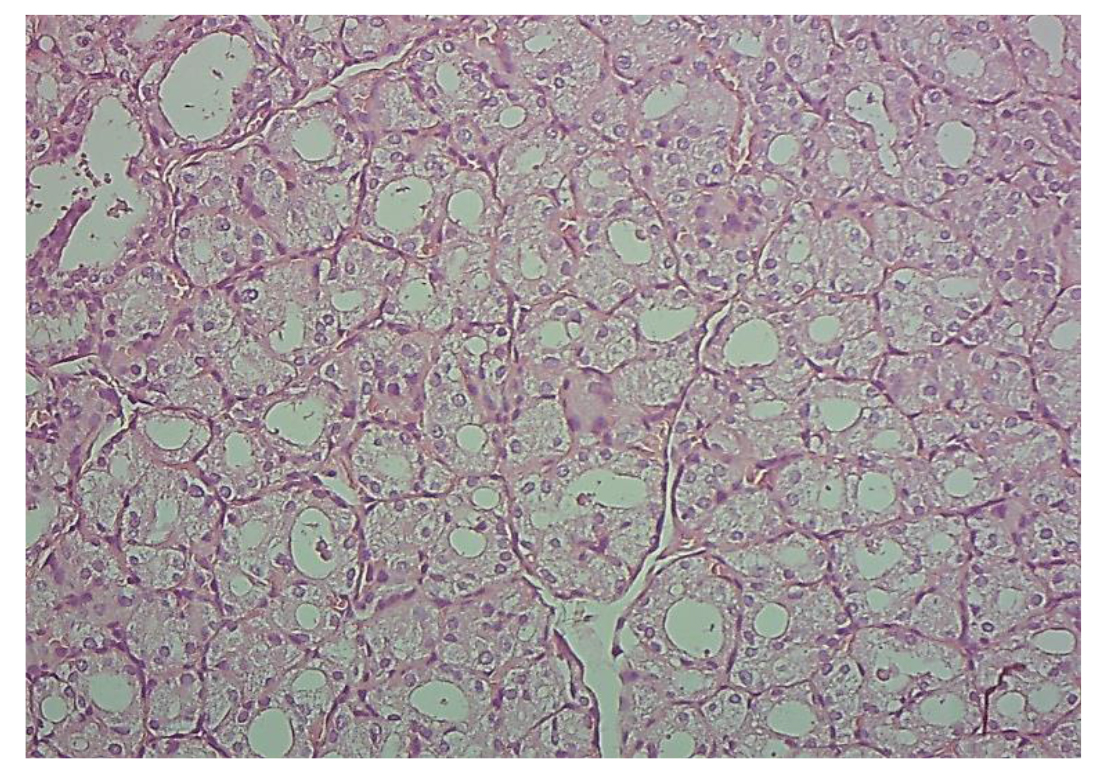

Histopathological study of thyroid section:

Figures 5, 6, 7, 8 , and 9 present light micrographs of the thyroid gland tissue samples stained with hematoxylin and eosin (H& E) at a magnification of 40X. Figure 5 illustrates the thyroid architecture of group G1 (control). The thyroid follicles in this group exhibit a normal parenchymal structure, characterized by intact, circular or oval shapes that vary in size, are filled with colloid, and are surrounded by a thin layer of cuboidal epithelial cells.

In contrast, Figure 6 depicts the thyroid sample from group G2, which exhibited significant destructive alterations in the thyroid parenchyma, evidenced by irregularly shaped follicles, a high proportion of follicle lumens with diminished or diffuse colloid, and some empty lumens encircled by a single layer of flattened cells.

Furthermore, degenerative changes were observed in the connective tissue within the interfollicular spaces. Figure 7 shows the thyroid section from group G3, indicating a restoration of the architectural integrity of the thyroid follicles, which were filled with colloid and lined by a cuboidal epithelial layer. Figure 8 presents the thyroid sample from group G4, revealing some thyroid follicles filled with colloid, alongside evidence of some hemorrhage. Finally, Figure 9 illustrates the thyroid tissue from group G5, demonstrating normal thyroid follicles filled with colloid.